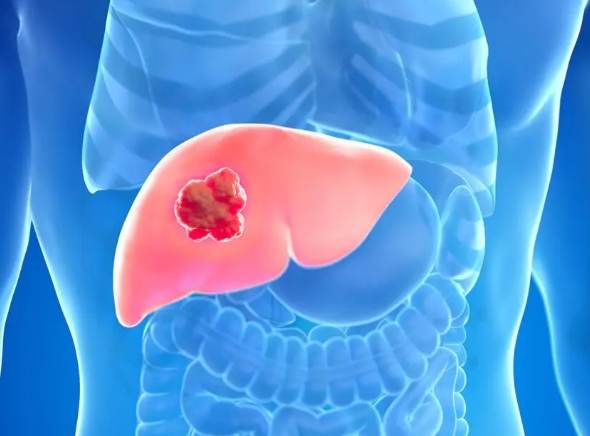

簡單來說,肝癌失能就是肝臟功能嚴重受損,導致身體無法正常運作的一種狀態。這不是突然發生的,而是一個漸進的過程,就像手機電池慢慢老化一樣。

肝癌失能的具體表現,比你想象的更細緻

很多人以為肝癌失能就是躺在床上不能動,其實遠不止如此。我見過一些患者,外表看起來還好,但內在的機能已經在悄悄罷工。